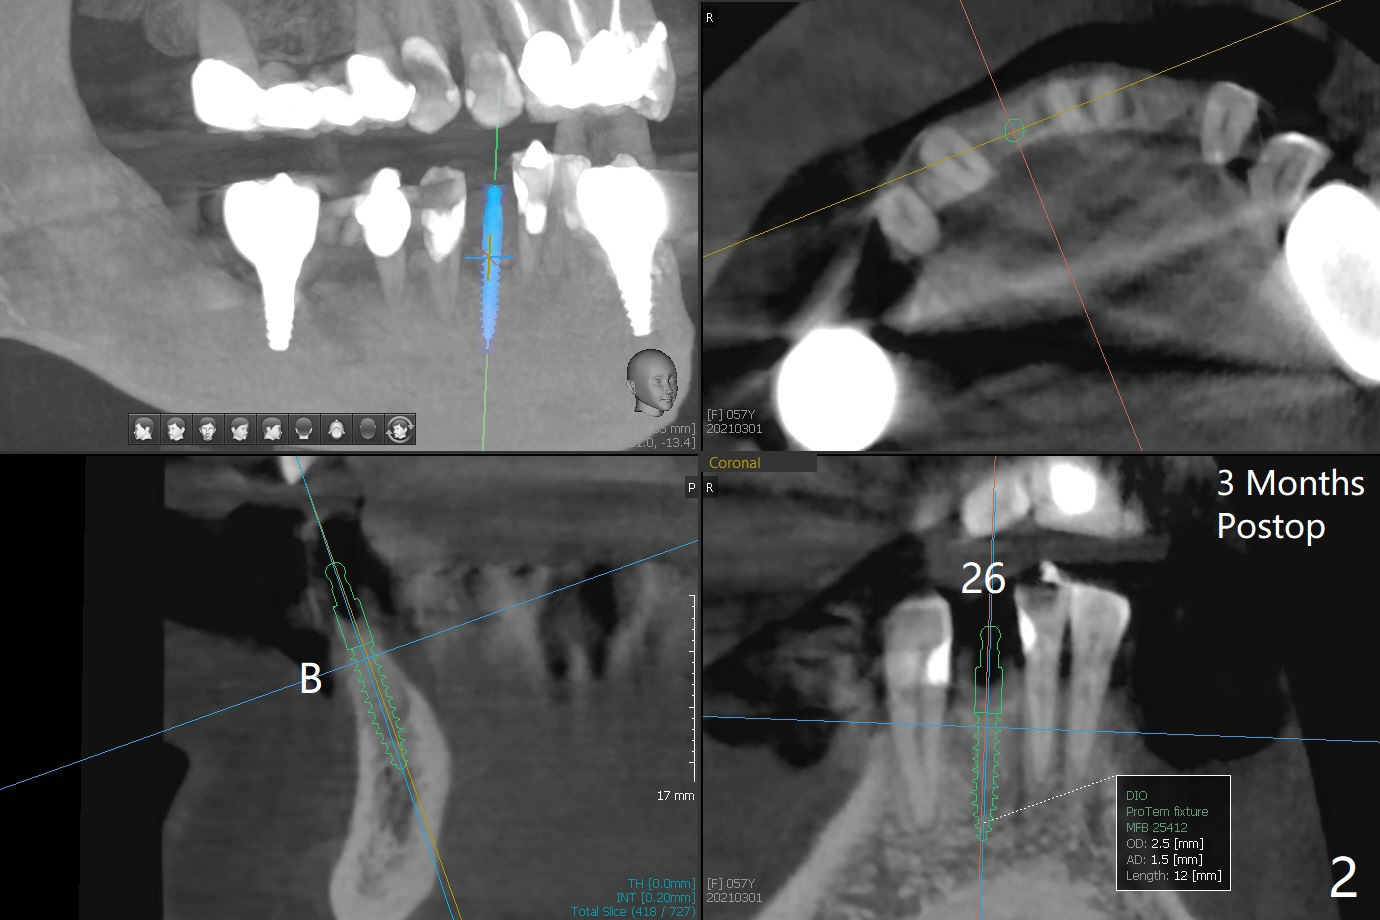

57岁女,口干症,前一个月(23,29号牙),三个月(26号牙)拔除植骨,可能需要再等一个月(出差)才能手术,会不会太早植牙?骨质还不够